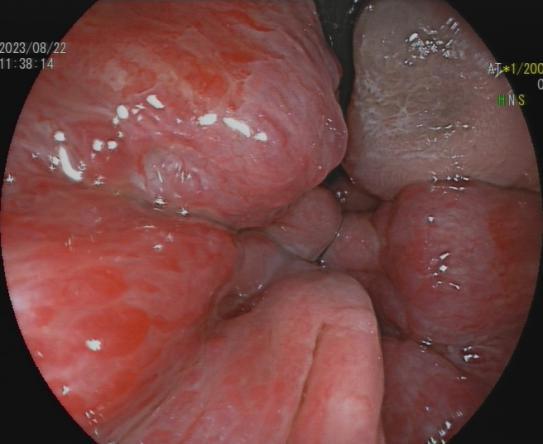

放大内镜下可见不规则微结构 BLI模式下可见不规则微血管

可清晰显示胃肠黏膜的腺管开口和微细血管等微细结构的变化,能比较准确地反映病变组织的病理学背景,区分增生性、腺瘤性和癌性病变,提高平坦和凹陷性早期癌的检出率,对消化道疾病的诊断及治疗具有重要的价值。